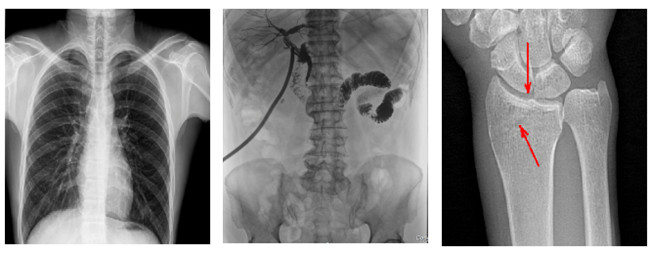

普利德多功能懸吊動(dòng)態(tài)DR,搭載100μm高品質(zhì)動(dòng)態(tài)平板探測(cè)器,不僅滿足常規(guī)的數(shù)字化X線全身攝影需求,同時(shí)還擁有數(shù)字?jǐn)z影、數(shù)字透視、數(shù)字造影、全景拼接等多種功能,極大地拓展了X線檢查在臨床應(yīng)用范圍,為醫(yī)院臨床應(yīng)用帶來(lái)更多實(shí)用價(jià)值?;诎傥⑵桨宓母咔宄上瘢瑘D像清晰度與分辨率更高,可滿足不同檢查部位對(duì)細(xì)節(jié)成像的高品質(zhì)要求,在胸腹部、脊柱等復(fù)雜骨骼和軟組織的攝片上應(yīng)用,更便于觀察隱匿性病灶,精準(zhǔn)識(shí)別疑難病癥。

不同于靜態(tài)DR拍攝隱匿性病灶時(shí),由于組織重疊病灶難辨,耗費(fèi)時(shí)間更長(zhǎng)且易漏診、誤診,普利德多功能懸吊動(dòng)態(tài)DR可通過(guò)動(dòng)態(tài)實(shí)時(shí)連續(xù)成像,對(duì)于重疊部位病灶或者易被遮擋的病灶進(jìn)行多角度動(dòng)態(tài)觀察,毫秒級(jí)時(shí)間內(nèi)實(shí)現(xiàn)動(dòng)靜態(tài)轉(zhuǎn)換點(diǎn)片,快速、精準(zhǔn)完成攝片。比如隱匿性肋骨骨折,可在透視下觀察患者的呼、吸過(guò)程,避開(kāi)重疊影像,快速點(diǎn)片,保證檢查部位的病癥不被遺漏,實(shí)現(xiàn)精準(zhǔn)診斷。